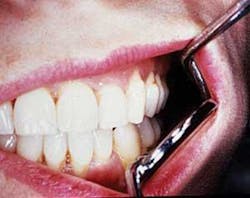

Fibrotic tissue exhibited by the tan band around the midline-inner part of the lip.

Perioral and intraoral characteristics: Depending upon the extent of the disorder, the patient may exhibit constriction of the mouth (microstomia) and an inability to close the lips, due to the amount of fibrosis (see Figures 1 and 2). In Figure 1, a band of thick fibrotic tissue is evident on the lip extending to the wet line of the lip. In Figure 2, the skin and oral tissues are tight even with the aid of mirrors. Leader5 suggests a physical therapy technique used to increase the mouth opening over time: Lubricate the mouth, have the patient cross arms at chest height, with palms facing down, and use the thumbs to stretch the corners of the mouth for several minutes. Over time, the tissue may become more flexible. TMJ problems may be pronounced due to tissue constriction.

The patient presented in Figure 1 has had some grafting performed because of recession. Rigidity of the tongue and xerostomia are continuing major problems for the patient. Sjogren's syndrome is common, producing dryness in all salivary tissue and lacrimal glands.